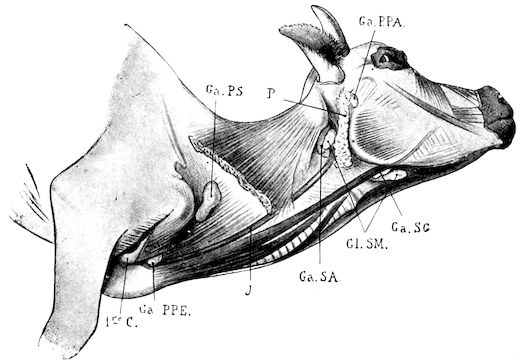

| II. | DISEASES OF THE SALIVARY GLANDS, TONSILS AND PHARYNX | 134 | ||

| Parotiditis (Parotitis) | 134 | |||

| Acute parotiditis | 134 | |||

| Chronic parotiditis—Parotid fistula | 136 | |||

| Inflammation of the submaxillary salivary gland | 137 | |||